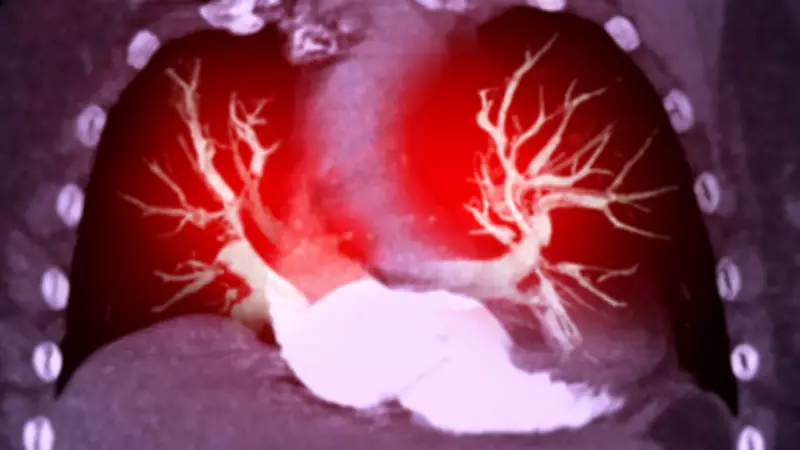

Pulmonary embolism occurs when a blood clot, typically originating in the leg veins, travels to the lungs and blocks pulmonary arteries. This blockage reduces blood flow and oxygen levels while increasing pressure on the heart. The condition can develop rapidly and prove fatal if not treated promptly.

"When a clot of blood in your leg vein travels to the lungs and causes blockage of a pipe going to the lung, this is called a pulmonary embolism," explains Dr. Ranjan Modi, Senior Consultant-Interventional Cardiology at Medanta Hospital Noida. "PE causes blood flow to be reduced and therefore, there is less oxygen in the blood. The pressure on the heart will increase. PE can develop very quickly and can be fatal."